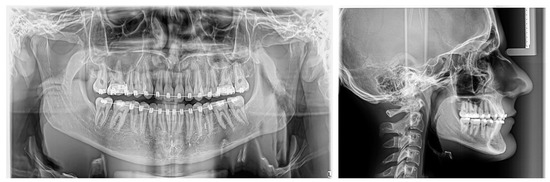

2.1. Examination, Diagnostics, and Initial Therapeutic Management